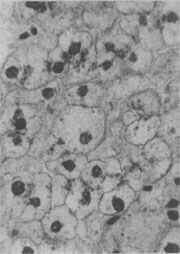

肾近曲小管上皮细胞玻璃样小滴变

图1-21 肾近曲小管上皮细胞玻璃样小滴变

上皮细胞胞浆内出现大小不等的均质圆形小滴

3.细胞内玻璃样变:亦称为细胞内玻璃样小滴变性。这种情况常见于肾小球肾炎或其他疾病而伴有明显蛋白尿时。此时肾近曲小管上皮细胞胞浆内可出现许多大小不等的圆形红染小滴(图1-21),这是血浆蛋白经肾小球滤出而又被肾小管上皮细胞吞饮的结果,并在胞浆内融合成玻璃样小滴,以后可被溶酶体所消化。此外,在酒精中毒时,肝细胞核周胞浆内亦可出现不甚规则的红染玻璃样物质。电镜下,这种物质由密集的细丝构成,据认为可能是细胞骨架中含角蛋白成分改变的结果,并被称为Mallory小体。